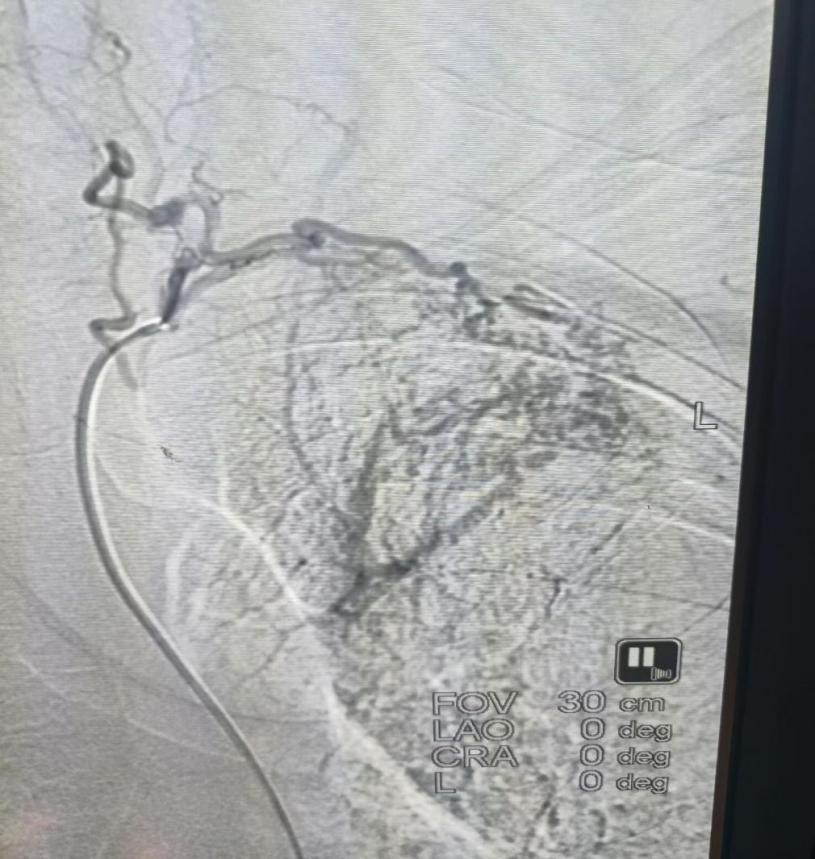

患者谭某因反复咯血入院,每次咯血量约200—300毫升。经询问,患者既往无支气管扩张等相关病史。为明确出血原因,在科主任副主任医师肖朝辉的带领下,介入团队对患者病情进行全面评估,并在局部麻醉下实施血管造影检查。

术中发现,患者左肺上叶的异常供血来源于一条罕见责任血管——“甲颈干”,且伴有动静脉瘘形成,终于找到导致反复咯血的直接原因。面对这一少见的解剖变异,介入团队沉着应对、精准定位,成功对左侧胸廓内动脉及相关支气管动脉远端实施栓塞治疗。